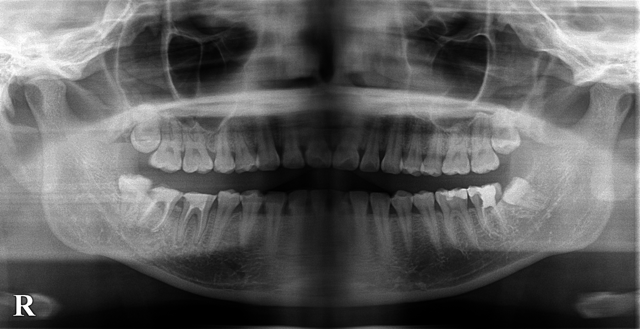

前歯の歯根嚢胞の経過(口腔外科)

今回は前歯の歯根嚢胞の経過をおったレントゲンをとってみました。 初診時に前歯が折れたということで来院された患者様です。レントゲンを撮影してみると根っこの先に歯根嚢胞というおおおきな病巣が認めれたため歯の保存は困難と判断し […]